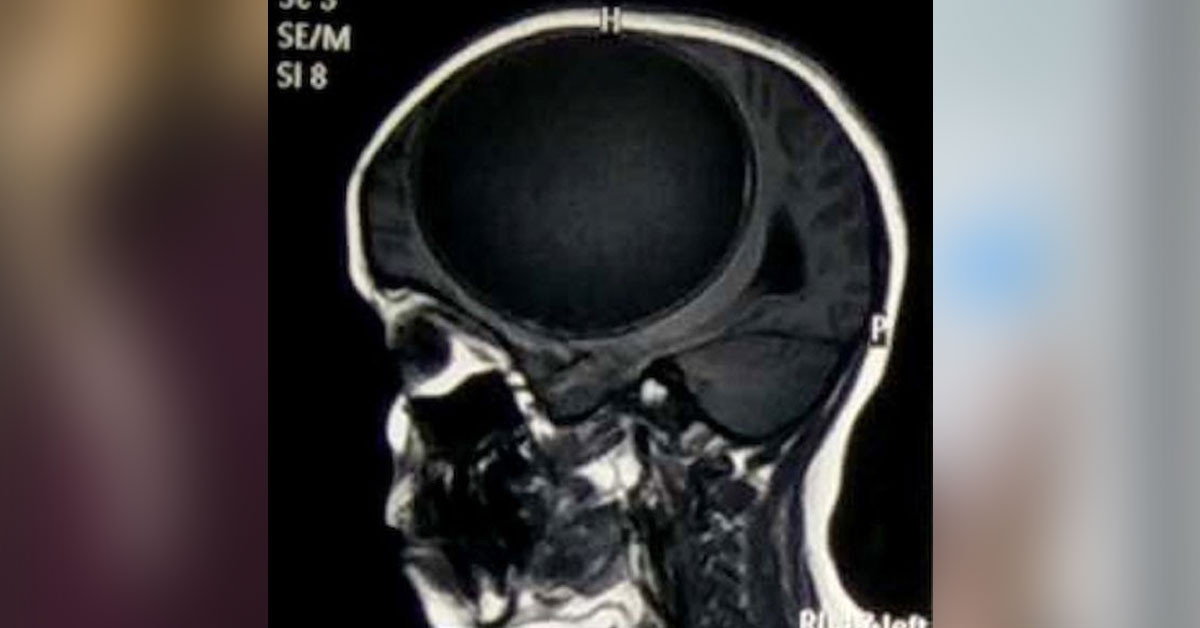

12 yaşında olan Nita Juggi isimli 12 yaşındaki küçük kız sürekli nöbet halinde ve 12 aydır vücudunun bir tarafı felçli bir şekilde yaşamını sürdürüyordu. Aile daha fazla dayanamadı ve maddi zorluklara rağmen kzılarını doktora götürdü. Doktora başvurduktan sonra yapılan çeşitli tahlillerden sonrasında küçük kızın beyninin yarısını kaplayan tenya yani bağırsak kurdu larvalarından kaynaklı merkezi sinir sisteminde sistiserkoz adı verilen bir teşhis koydu.

Küçük kızın beyninde o kadar büyük bir larva vardı ki her an patlamaya hazır bir bomba gibiydi.

Bir bağırsak kurdunun larvasının sebep olduğu rahatsızık yüzünden ölümden dönen kız hemen ameliyata alındı.

Oldukça riskli geçen ameliyat sonrası genç kız eski sağlığına kavuştu.